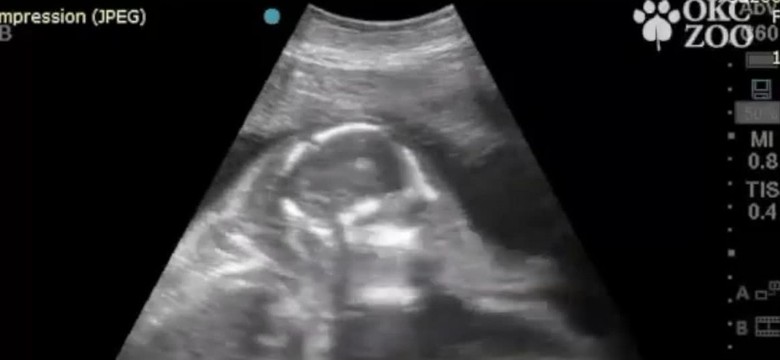

Widzę tu próbę przesunięcia odpowiedzialności na lekarzy i radykalnego zmniejszenia katalogu wad, które kwalifikowałyby do terminacji ciąży – mówi dr Piotr Kretowicz, specjalista w zakresie położnictwa i ginekologii, ultrasonografii oraz diagnostyki prenatalnej. Zajmuje się patologią ciąży, diagnostyką oraz terapią wad wrodzonych i chorób płodu.